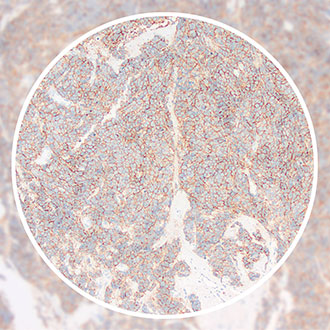

阳性对照:小细胞肺癌

CD56,为神经细胞粘附分子(Neural Cell Adhesion Molecule,NCAM),分子量140 kDa,是一组相关的细胞表面糖蛋白。主要表达在神经元、星形细胞、施万细胞、NK 细胞和小部分活化的T细胞中,在胚胎发育以及神经细胞的相互联系中发挥重要作用。CD56抗体可用于诊断神经外胚层肿瘤、小细胞肺癌和NK 细胞淋巴瘤,也可以辅助诊断甲状腺乳头状癌。